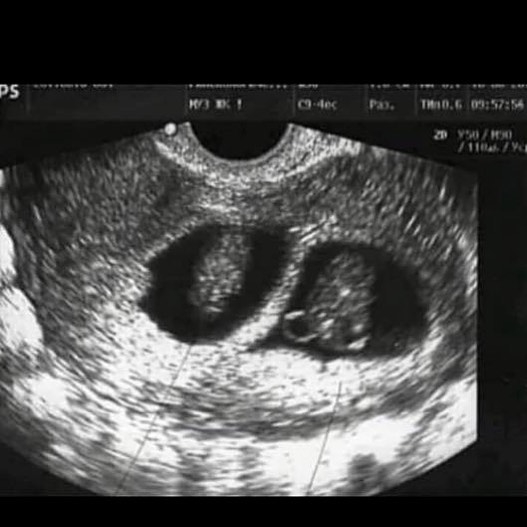

Девчульки , конец года застал меня врасплох, встретил приятным сюрпризом. Эти два маленьких комочка лежат тут уже 7недель, но мы ничего не знали. Конечно, у нас сначала был шок , но мы все равно очень рады , особенно потому,что их там двое. Мы даже не знаем , девочки это или мальчики Или девочка и мальчик . мы бесконечно счастливы . Конечно это может произойти с любой женщиной . И пусть у тебя , кто мечтает о таком счастье, оно обязательно сбудется. К сожалению , я не знаю , кто их родители , но...